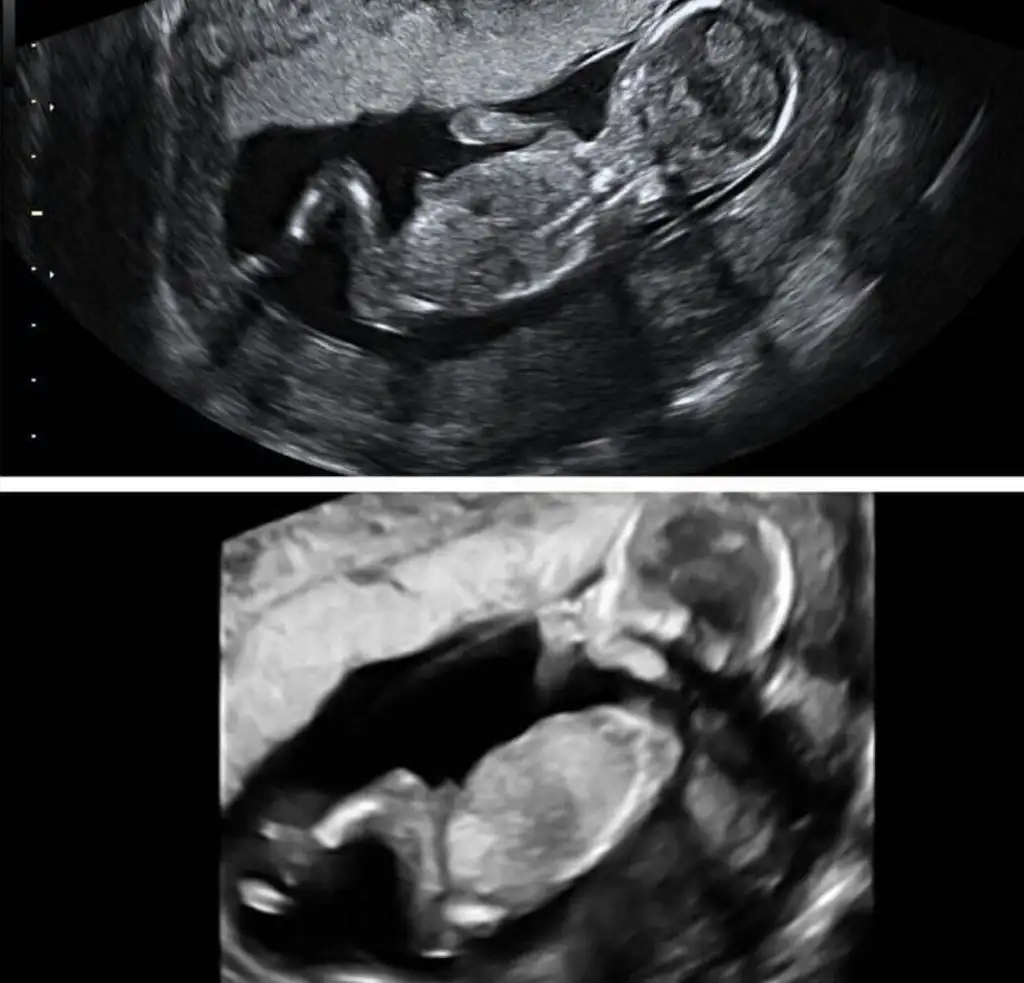

Merhaba hanımlar yeni üyeyim ilk hamileligimi yaşıyorum 16+5 haftalık hamileyim dün kontrolum vardi şükür bebeğim çok iyi ama cinsiyetini ogrenemedik doktorum bi yorumda bulunmak istemediğini tam emin olduğunda söylemek istediği söyledi eşim ve benim için öncelik tabii sağlıklı olması ama ilk olunca insan cok heyecanlı ve merakli oluyor .Bazen karın yapisindan ve ultrasondan anlayanlar oluyor tecrübeli annelerden yorum bekliyorum

Bizde daha yeni öğrenebildik :) hiç benzetme yapmadı mı Yani bana kıza benziyor dediler sonra acaba erkek mi filan dediler salı günü ayrıntılı ultrasonda netleşti.

Sizinde kız gibi sanki :))

sorma canim ya boyle oldukca daha cok heyecanlandırdi bizi bence doktorum gördü anladi ama emin olmak icin beklemek istedi diger kontrolu karnima koyunca direkt gülmeye basladi ben hemen anladim dedim noldu belli etmis mii az cok bi tahminim var ama tam acik degil bacağını koymus dedi bekledi karnimda bayağı bebek oynasin diye ama yok donmedi bebek ben simdi tam emin olmadan tahminimi soylemek istemiyorum diyodu ama gülüyor soylerken

Ben pek anlamam ama bence kız olabilirrr...

Keşke söylese :) daha çok meraklandırmak istemiş sanırım genellikle benziyor dedikleri cinsiyet çıkıyor Allah sağlık versin en önemlisi o.

Bana kız gibi geldi hayırlısı bakalım:)

Herkes kız tahmininde bulunmuş

Ama ben herkesten farklı olarak erkek diyeceğim bakalım ne çıkacak Hayırlısı olsun insAllah